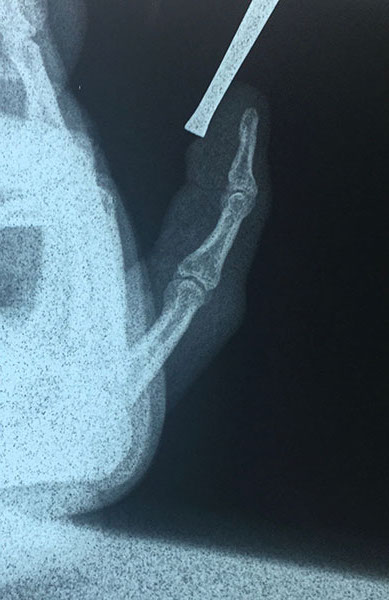

Nuestro paciente mientras ayudaba con el levantamiento de una maquinaria pesada sufre un accidente en que dicha maquina cae sobre su dedo meñique, tras esto se da cuenta que el dedo se ha estallado dejando ver su hueso y una importante herida, nota además deformidad del dedo, es llevado de inmediato a un hospital de la ciudad donde tras ser evaluado y hacerle radiografías le sugieren realizar amputación del dedo pero el paciente no la acepta y decide comunicarse conmigo como cirujano especialista en mano.

Evalué al paciente y siempre pensando en salvar el dedo de la amputación lo lleve a quirófano ese mismo día en horas de la noche, tras una buena limpieza de las heridas encontramos una luxación del dedo y redujimos la misma reparando la parte ligamentaria, mantuvimos al paciente hospitalizado durante 24 horas en que recibió antibióticos y controlamos el proceso de hinchazón del dedo.